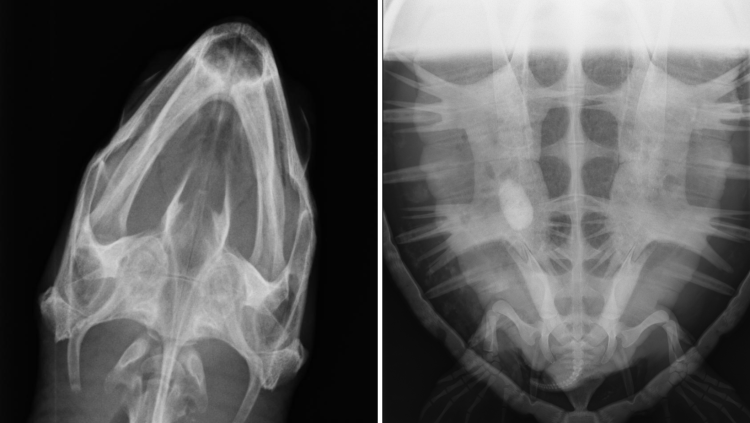

X-rays allow us to look into the internal structures (bones and organs) of any new sea turtle patients received into our care. The arrival X-ray of Kijani will act as a baseline to refer back to for any changes that may be observed during her continued rehabilitation and recovery time.